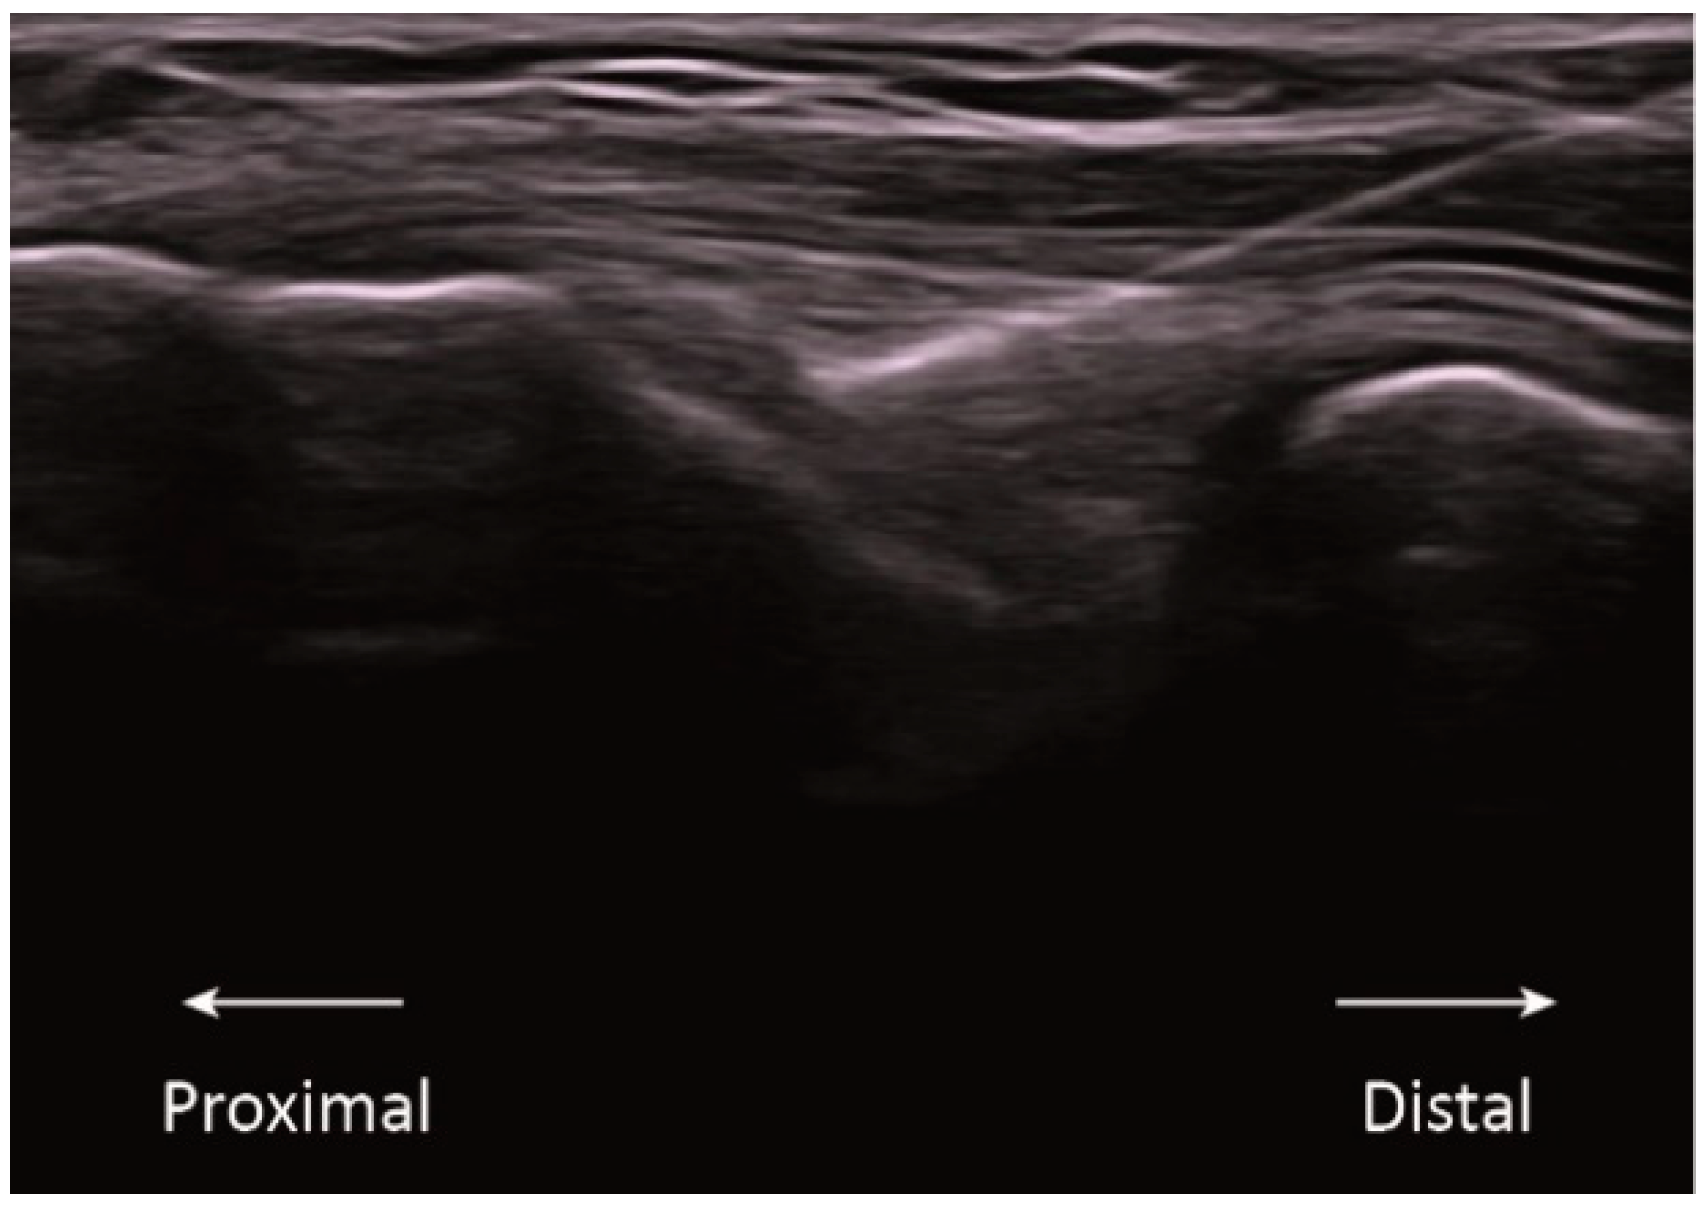

This randomized clinical trial had three groups: sham, low intensity, and high intensity. All groups received a single session of an ultrasound-guided needle intervention on the common extensor tendon of the lateral epicondyle of the right side. The intervention was performed by a physical therapist with more than 10 years of experience in the technique. Participants were lying comfortably in a supine position with the right elbow on the table in a position of 20° flexion and with the forearm pronated. As described by Rodríguez-Huguet [13], a 0.3 × 25 mm acupuncture needle (Agupunt, Barcelona, Spain) was inserted under ultrasound guidance at 45° to the skin in the direction of the lateral epicondyle to reach the deep surface of the common extensor tendon (Figure 1).

Figure 1.

Ultrasound imaging of the application of percutaneous electrolysis in the common extensor tendon of the lateral epicondyle.